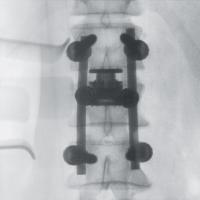

手術室内で移動式のX線装置を使用して行う撮影です。

直接目視できない部分をX線画像でリアルタイムに見られるため、より安全に手術を行うサポートができます。

一例として、金属のボルトを骨内に挿入する際に、位置や角度、深さを様々な方向から観察できるほか、装置を回転させて撮影することで、CT画像のような自由な断面像を得ることも可能です。